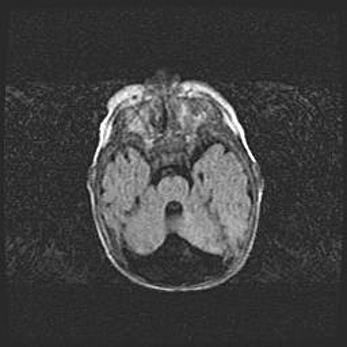

Подострая гематома правой гемисферы мозжечка.

Наружная гидроцефалия.

Возраст: 15 дней

Вес: 3100 г

Пол: женский

Окружность головы: 37 см

Срок гестации: 35-36 недель

При открытой наружной форме гидроцефалии у новорожденных расширяются и переполняются субарахноидные пространства.

Кровоизлияния в мозжечок имеют две клинико-анатомические формы: полушарные гематомы и кровоизлияния в червь.

К появлению этой патологии может привести: повреждения головного мозга, возникающие в результате асфиксии и гипоксии плода при беременности, или травмы во время родов. Редко гематома мозжечка может быть результатом первичной коагулопатии и сосудистой мальформации, диссеминированном внутрисосудистом свертывании, изоиммунной тромбоцитопении.